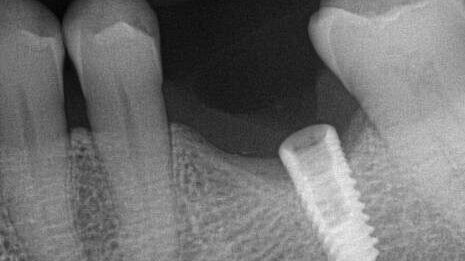

This implant case showcases an example of an Iatrogenic screw retrieval of a poorly placed TSV implant, Creating a Type VI Screw Recovery Case.